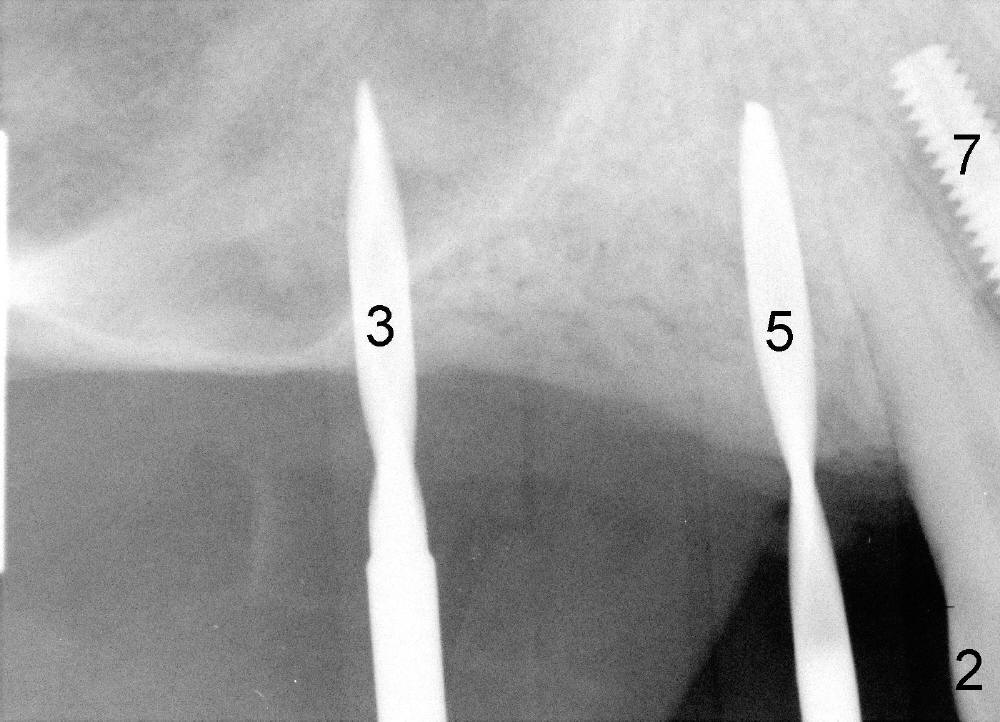

It appears that sinus graft is necessary for #3-5 implant placement (Fig.1). Mr. Wu says "Do whatever you think appropriate." But the framework partial denture is suddenly broken at the major connector. He cannot eat well. We do not have time to do sinus graft! Short implant is planned to be placed at the site of #3 (5x11 mm, Fig.1). After initial bone expansion until RT 2 mm (as mentioned above), two-mm pilot drills are inserted at the sites of #3 and 5 (Fig.2). The sinus floor is perforated at #3. The osteotomy for #3 is then moved mesially ~ 2 mm using osteotomes (RT 2-4mm). While bone expansion (osteotomes and taps) is being used to create osteotomy for #3, tapered drills for #5. Fig.3 shows 5x11 mm tap and 3.5x20 mm drill in place. Finally 6x11 mm and 4x20 mm implants are placed with >60 Ncm (Fig.4). The patient is also doing great nearly two weeks postop. A third implant is planned to be placed at the site of #5 1-3 months later.